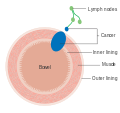

Dukes stage B bowel cancer; the cancer has invaded the muscle. Dukes stage C bowel cancer; the cancer has invaded the nearby lymph nodes.

Dukes stage C bowel cancer; the cancer has invaded the nearby lymph nodes. Dukes stage D bowel cancer; the cancer has metastasized.